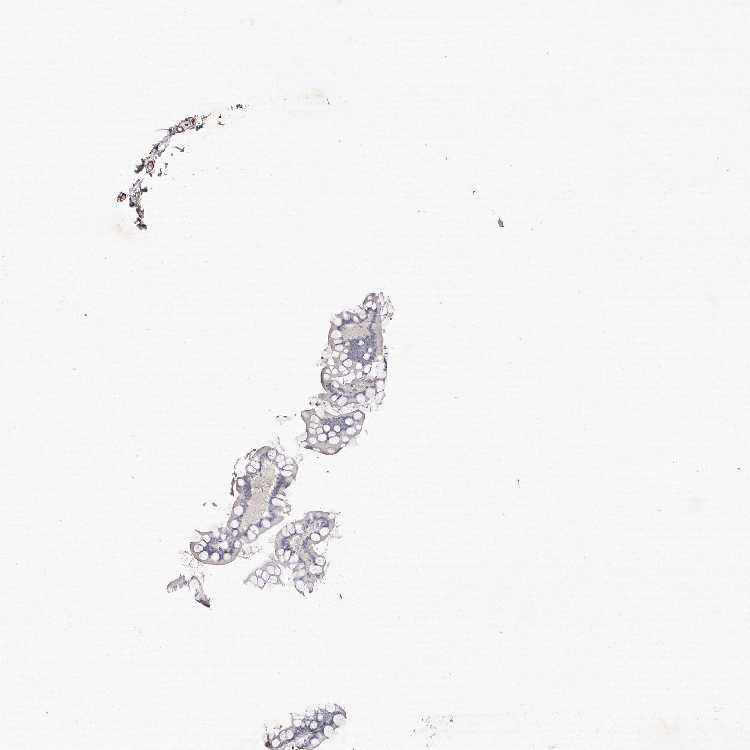

SMALL INTESTINE - Antibody stainingi

Antibody staining in the annotated cell types in the current human tissue is reported as not detected, low, medium, or high, based on conventional immunohistochemistry profiling in selected tissues. This score is based on the combination of the staining intensity and fraction of stained cells.

Each image is clickable and will lead to virtual microscopy that enables deeper exploration of all samples and also displays staining intensity scores, fraction scores and subcellular localization as well as patient and tissue information for each sample.

Antibody HPA028325Antibody HPA028435Antibody HPA030097

Glandular cells Not detectedNot detectedNot detected